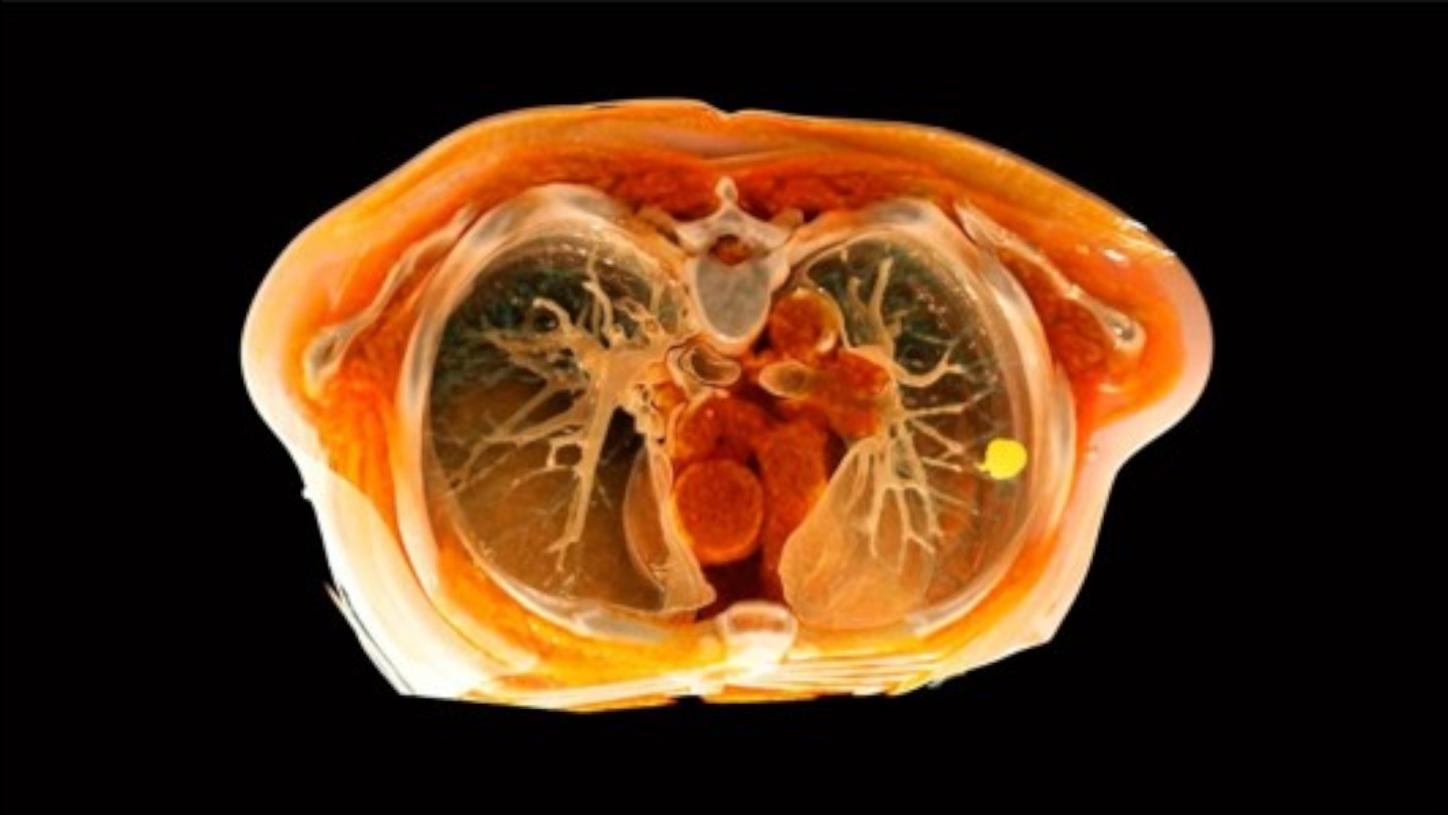

https://www.lung.org/lung-health-diseases/lung-disease-lookup/lung-cancer/resource-library/lung-cancer-fact-sheet